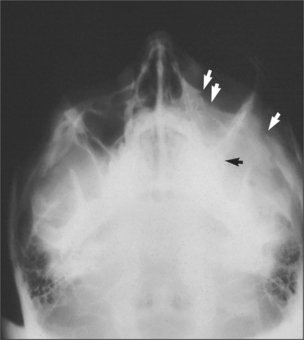

mid-face: two occipitomental views at different angles (Fig. 13.6)

Page 190

image

Fig. 13.6 Occipitomental view of fractured zygoma. Arrows indicate fractures at the infraorbital rim, zygomatic arch and zygomatic buttress areas.

Radiographs may be necessary not only to reach a diagnosis but also to inform treatment decisions, for example, about where bone plates should be applied. They also commonly reveal injuries which may not need treatment, for example, undisplaced or minimally displaced fractures, medial blow-out fractures of the orbit and comminution of the mid-face. Radiographs provide much more detailed information on hard-tissue injuries than the clinical examination so they may, for example, show fractures of the roots of teeth and signs of associated soft-tissue abnormality, such as herniation of orbital contents into the maxillary antrum (Figs 13.9, 13.10).